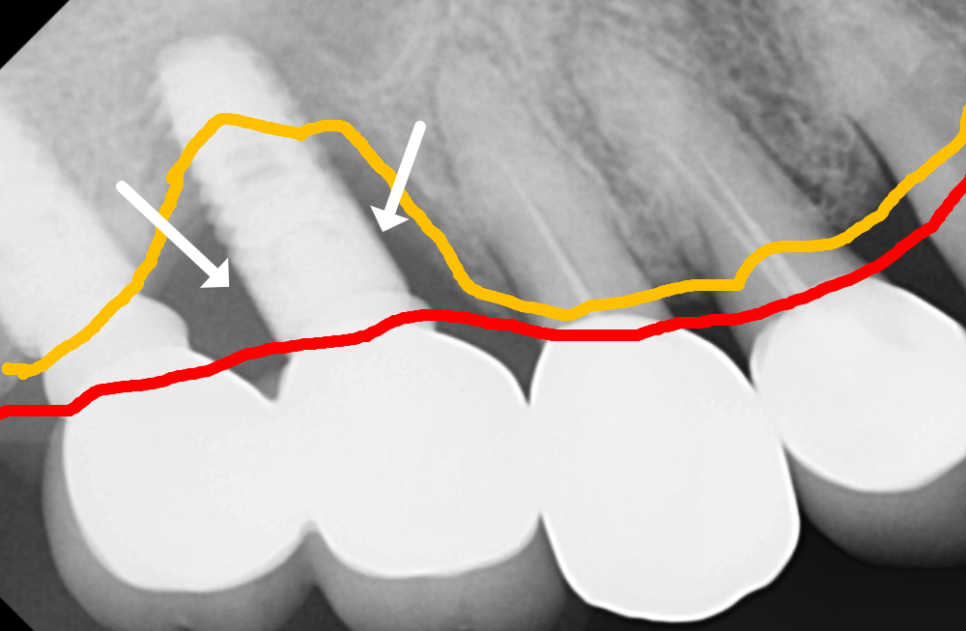

과거의 일반적인 임플란트 방식은

의료진의 경험과 2차원적인 엑스레이에

의존해 식립 위치를 결정하는 경우가 많았어요.

이 환자분 케이스에서 가장 중요했던 점은

아래턱을 지나는 하치조 신경을

완벽히 피하는 것인데요.

만약 임플란트가 이 신경을 조금이라도 건드리면

안면 마비나 감각 이상 같은

심각한 부작용이 생길 수 있기 때문에

주의해야 하는 구조물 중 하나입니다.

일반적인 방식이었다면

의사의 감각에 의존해 신경관과의 거리를

가늠하며 조심스럽게 심었겠지만...